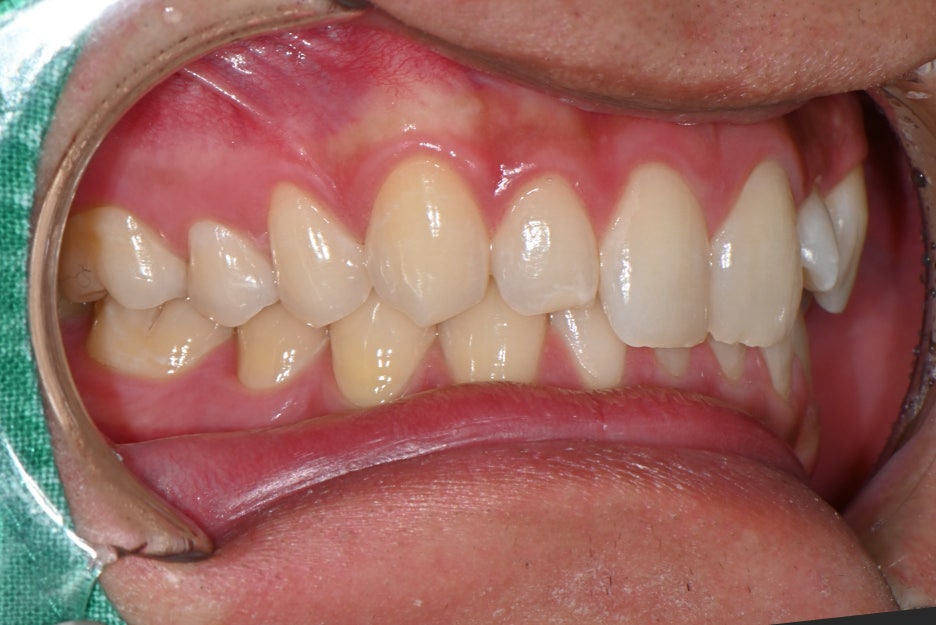

In particular, the small teeth located next to both front teeth

appeared to be naturally small in shape,

and the color did not match, so overall,

his smile looked dull.

In cases like this, rather than making excessive shape changes,

a custom design centered on naturalness is needed,

so Object Zero Laminate (OVZERO) was appropriate.